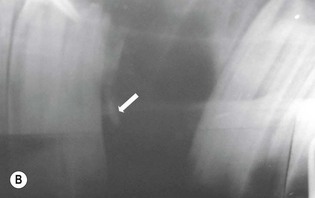

image

(B) Intra-oral radiograph taken intra-operatively during a dental extraction procedure. A small bone-opacity fragment can be seen in the rostral aspect of the alveolus (arrow).

(Radiograph courtesy of W.H. Tremaine.)